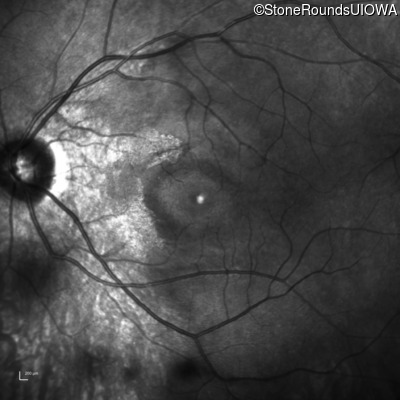

OD OS

This fourteen year old female has had poor vision in dim light since at least age 6.

Diagnosis & molecular findings

Congenital Stationary Night Blindness SLC24A1 Glu801 del4gAAGGinsTT Asn893 del1aaT AR